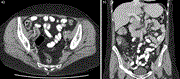

An unusual case of abdominal compartment syndrome from a massive faecaloma

Fred Jui-Ju Chuang and others

Journal of Surgical Case Reports, Volume 2022, Issue 8, August 2022, rjac348, https://doi.org/10.1093/jscr/rjac348